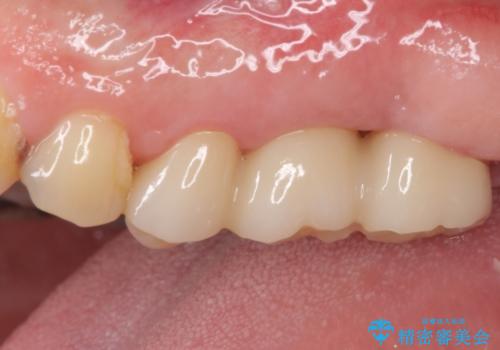

痛みは速やかに引き、銀歯や黒く変色したむし歯がセラミッククラウンで自然な色合いに仕上がり、患者様には大変満足していただきました。